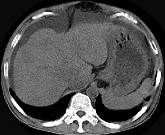

- 单项选择题男,44岁, 有乙肝病史,现腹胀, 右上腹痛,消化不良, 消瘦、乏力、贫血、黄疸,血清转氨酶升高, 清蛋白/球蛋白比值倒置。CT、MRI检查如下图,最准确的诊断是 ( )

A、肝硬化并腹水

B、肝硬化并腹水、再生结节

C、肝硬化腹水、肝癌

D、肝硬化并再生结节

E、肝硬化并腹水、脂肪肝